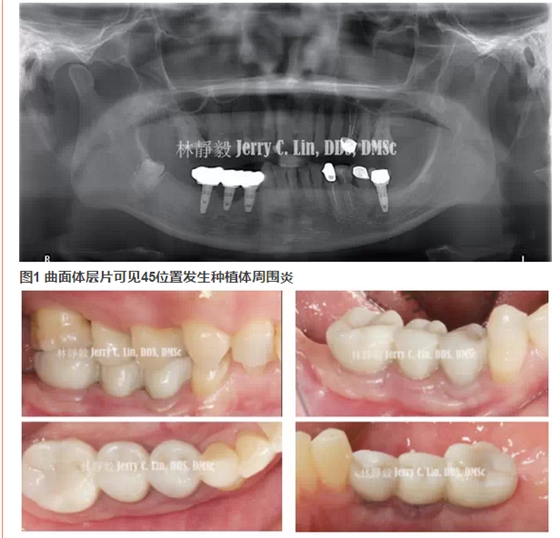

【口腔種植】嚴(yán)重種植體周圍炎的處理(二)——林靜毅醫(yī)師